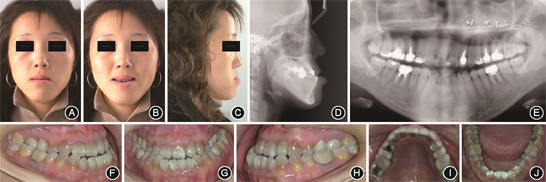

(1)颜面检查:正面观左右基本对称;侧面观为凹面型,鼻旁区凹陷,颏部前突。

(2)口内检查:恒牙列,12缺失,上下牙弓尖圆形,下前牙拥挤;上中线较面中线右偏3 mm,下中线与面中线基本对齐;双侧磨牙为近中关系;前牙覆

0 mm,反覆盖2 mm;全口牙颈部颜色发黄,口腔卫生良好。

(3)颞下颌关节检查:开口度正常,开口型正常,双侧颞下颌关节无张口弹响与杂音,无明显压痛。

(4)X线检查:头颅侧位X片及头影测量分析显示,患者为骨性Ⅲ类[ANB角(上牙槽座点、鼻根点与下牙槽座点构成的角)为-5.2°],高角型[FMA角(眼耳平面与下颌平面的交角)为40.6°],上颌骨发育不足,下颌骨发育过度,上切牙代偿性唇倾,下切牙代偿性舌倾。曲面体层X线片显示14、17、24、47冠内高密度影,15、16、22、25、26、36、46冠及根管内高密度影,余牙牙根未见明显异常;全口牙牙槽骨水平吸收;关节区未见明显异常(图1)。

成年患者治疗前面像、口内像和影像学资料 A:正面像;B:正面微笑像;C:侧面像;D:头颅侧位X线片;E:曲面体层X线片;F:右侧

像;G:正面

像;H:右侧

像;I:上颌

面像;J:下颌

面像

面像3.诊断:安氏Ⅲ类错